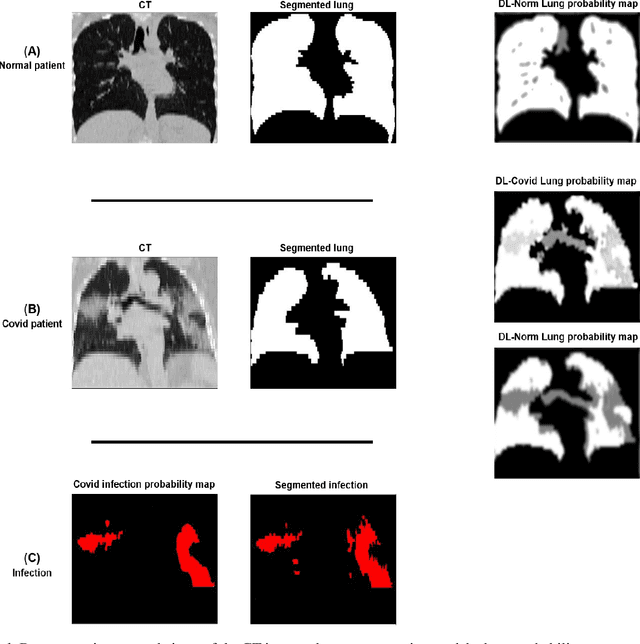

Abstract:This study aimed to evaluate the performance of a novel unsupervised deep learning-based framework for automated infections lesion segmentation from CT images of Covid patients. In the first step, two residual networks were independently trained to identify the lung tissue for normal and Covid patients in a supervised manner. These two models, referred to as DL-Covid and DL-Norm for Covid-19 and normal patients, respectively, generate the voxel-wise probability maps for lung tissue identification. To detect Covid lesions, the CT image of the Covid patient is processed by the DL-Covid and DL-Norm models to obtain two lung probability maps. Since the DL-Norm model is not familiar with Covid infections within the lung, this model would assign lower probabilities to the lesions than the DL-Covid. Hence, the probability maps of the Covid infections could be generated through the subtraction of the two lung probability maps obtained from the DL-Covid and DL-Norm models. Manual lesion segmentation of 50 Covid-19 CT images was used to assess the accuracy of the unsupervised lesion segmentation approach. The Dice coefficients of 0.985 and 0.978 were achieved for the lung segmentation of normal and Covid patients in the external validation dataset, respectively. Quantitative results of infection segmentation by the proposed unsupervised method showed the Dice coefficient and Jaccard index of 0.67 and 0.60, respectively. Quantitative evaluation of the proposed unsupervised approach for Covid-19 infectious lesion segmentation showed relatively satisfactory results. Since this framework does not require any annotated dataset, it could be used to generate very large training samples for the supervised machine learning algorithms dedicated to noisy and/or weakly annotated datasets.